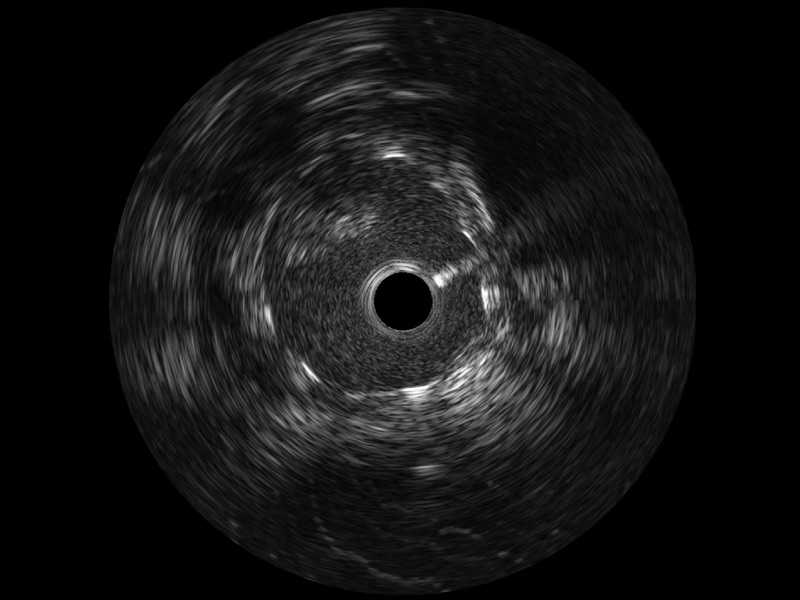

開立寬頻IVUS圖像

傳統(tǒng)IVUS圖像

對比傳統(tǒng)IVUS導(dǎo)管成像,開立寬頻IVUS圖像的近場支架梁顯影更細(xì)膩,遠(yuǎn)場中膜外血管仍清晰可辨,兼顧遠(yuǎn)中近,兼顧分辨力與穿透深度